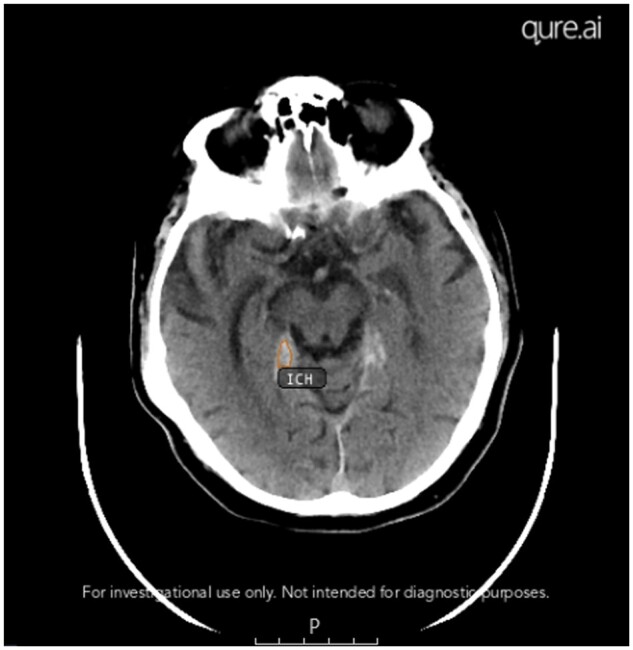

Objectives: Artificial intelligence (AI) algorithms have the potential to assist radiologists in the reporting of head computed tomography (CT) scans. We investigated the performance of an AI-based software device used in a large teleradiology practice for intracranial haemorrhage (ICH) detection.

Methods: A randomly selected subset of all non-contrast CT head (NCCTH) scans from patients aged ≥18 years referred for urgent teleradiology reporting from 44 different hospitals within the United Kingdom over a 4-month period was considered for this evaluation. Thirty auditing radiologists evaluated the NCCTH scans and the AI output retrospectively. Agreement between AI and auditing radiologists is reported along with failure analysis.

Results: A total of 1315 NCCTH scans from as many distinct patients (median age, 73 years [IQR 53-84]; 696 [52.9%] females) were evaluated. One hundred twelve (8.5%) scans had ICH. Overall agreement, positive percent agreement, negative percent agreement, and Gwet's AC1 of AI with radiologists were found to be 93.5% (95% CI, 92.1-94.8), 85.7% (77.8-91.6), 94.3% (92.8-95.5) and 0.92 (0.90-0.94), respectively, in detecting ICH. 9 out of 16 false negative outcomes were due to missed subarachnoid haemorrhages and these were predominantly subtle haemorrhages. The most common reason for false positive results was due to motion artefacts.

Conclusions: AI demonstrated very good agreement with the radiologists in the detection of ICH.

Advances in knowledge: Real-world evaluation of an AI-based CT head interpretation device is reported. Knowledge of scenarios where false negative and false positive results are possible will help reporting radiologists.